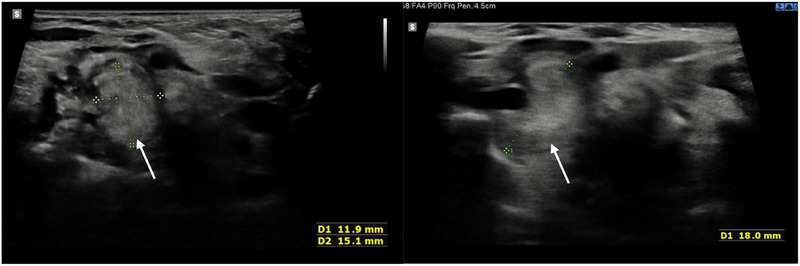

Case presentation: An 18-week-old boy presented with right peri-orbital swelling, initially thought to be pre-septal cellulitis. Further ophthalmic review revealed a right-sided HS. Imaging identified a probable cervical neuroblastoma, leading to an urgent referral to oncology.